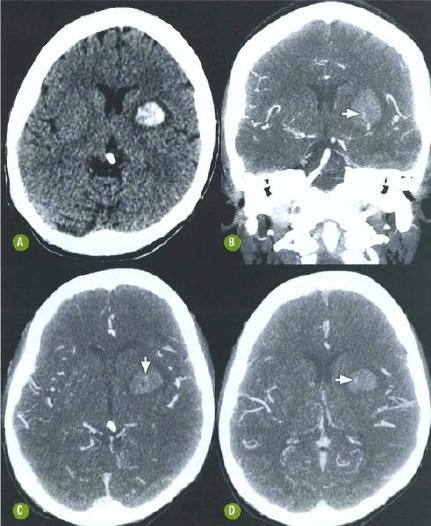

Paciente do sexo masculino, 57 anos, hipertenso e diabético, chega ao PA relatando cefaleia intensa, de início súbito, por vezes associada à tontura. Ao exame físico, nota-se pico hipertensivo.

Com base nas imagens tomográficas a seguir, é correto afirmar que